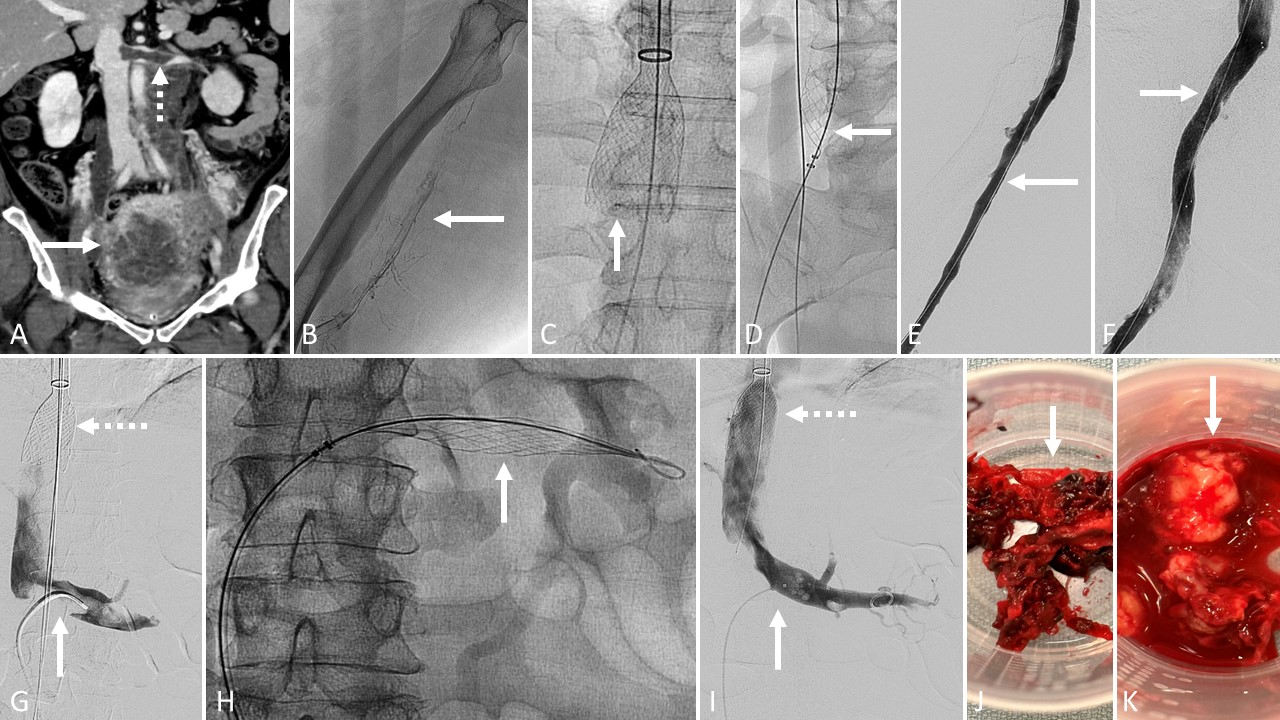

A 65-year-old female with a 2-year history of cholangiocarcinoma presented with new jaundice the day after a liver biopsy. Prior to the biopsy, the patient was taken off Eliquis, which she had been on prophylactically due to a liver mass causing compression of the IVC. In the emergency room, computed tomographic (CT) venography was performed, which showed thrombus within the intrahepatic IVC extending down to involve the left renal vein, the infrarenal IVC, and the right common iliac vein (A). The patient was started on a heparin drip, and interventional radiology was consulted for mechanical thrombectomy.

The initial plan was to access the right IJ vein and right common femoral vein. Once the patient was sterilely prepped and draped, the right IJ was accessed using a micropuncture needle. This was then transitioned up to an 8F sheath. Next, using a Berenstein catheter and a stiff Glidewire, the catheter wire combination was negotiated down the IVC and right iliac system without difficulty. Intravascular ultrasound was then performed over the wire from the cavoatrial junction through the right external iliac vein, followed by venography of the IVC (B).

A Berenstein catheter and Glidewire combination was then used to select the right common femoral vein. The catheter was placed into the popliteal vein, and the wire was exchanged for a superstiff Amplatz wire. The catheter was then removed.

The existing 8F right IJ sheath was then removed, the tract was dilated, and the 20F Protrieve sheath was placed (C). The funnel was deployed below the cavoatrial junction.

A 16F ClotTriever sheath was advanced into the Protrieve sheath in the right IJ, and the funnel was deployed. Then, the ClotTriever BOLD mechanical thrombectomy catheter was advanced over the wire (D). The coring element was deployed in the right common iliac vein. A total of 4 passes were performed, yielding 100% of the thrombus burden (E). The coring element was collapsed at the level of the Protrieve nitinol mesh funnel with each pass. Repeat venography and IVUS were performed, demonstrating no residual thrombus in the IVC (F). The ClotTriever sheath was then removed.

Attention was then turned to the left renal vein. Using a Berenstein catheter and glidewire, the left renal vein was selected. Contrast was injected through the catheter and a venogram of the left renal vein was performed (G). An Amplatz wire was then placed into the left renal vein, and great attention was paid to ensure that the wire would not advance to the renal hilum.

Next, a Triever20 catheter was advanced over the wire and parked within the ostium of the left renal vein. A total of 3 aspirations were performed. The aspirated contents were filtered through the FlowSaver Blood Return System, and blood was given back to the patient via the sideport of the Protrieve sheath. Repeat venography of the left renal vein was performed through the Triever20 catheter and then removed.

Stenting the intrahepatic IVC was the final step to help relieve the compression from the cholangiocarcinoma. After identifying appropriate landmarks using both venography and IVUS, a 16-mm x 60-mm Venovo stent was deployed in the intrahepatic IVC (H). The stent was then post dilated with a balloon and repeat venography and IVUS of the IVC was performed. The right IJ Protrieve sheath was removed after a purse string suture had been placed. Pressure was held for 15 minutes after the suture had been cinched. Thromboemboli were observed in the Protrieve funnel.

Discussion

The Protrieve sheath made it possible to simplify this complex case by using only one access site. It allowed us to use ClotTriever and FlowTriever from a right IJ approach to clear out thrombus that extended centrally from the right common iliac vein (I). Pathology confirmed the thrombus was bland and not from tumor invasion. The 1-month post-procedure CT venography demonstrates patency of the IVC stent (J; solid arrow), the remainder of the IVC, and left renal vein (J; dashed arrow).